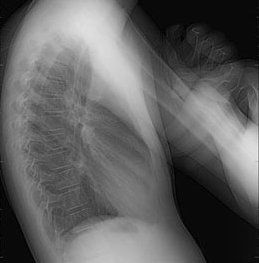

Radiologie Diagnostique

Pas de préparation spécifique, le patient sera debout ou allongé selon la région à explorer. L’examen est totalement indolore.